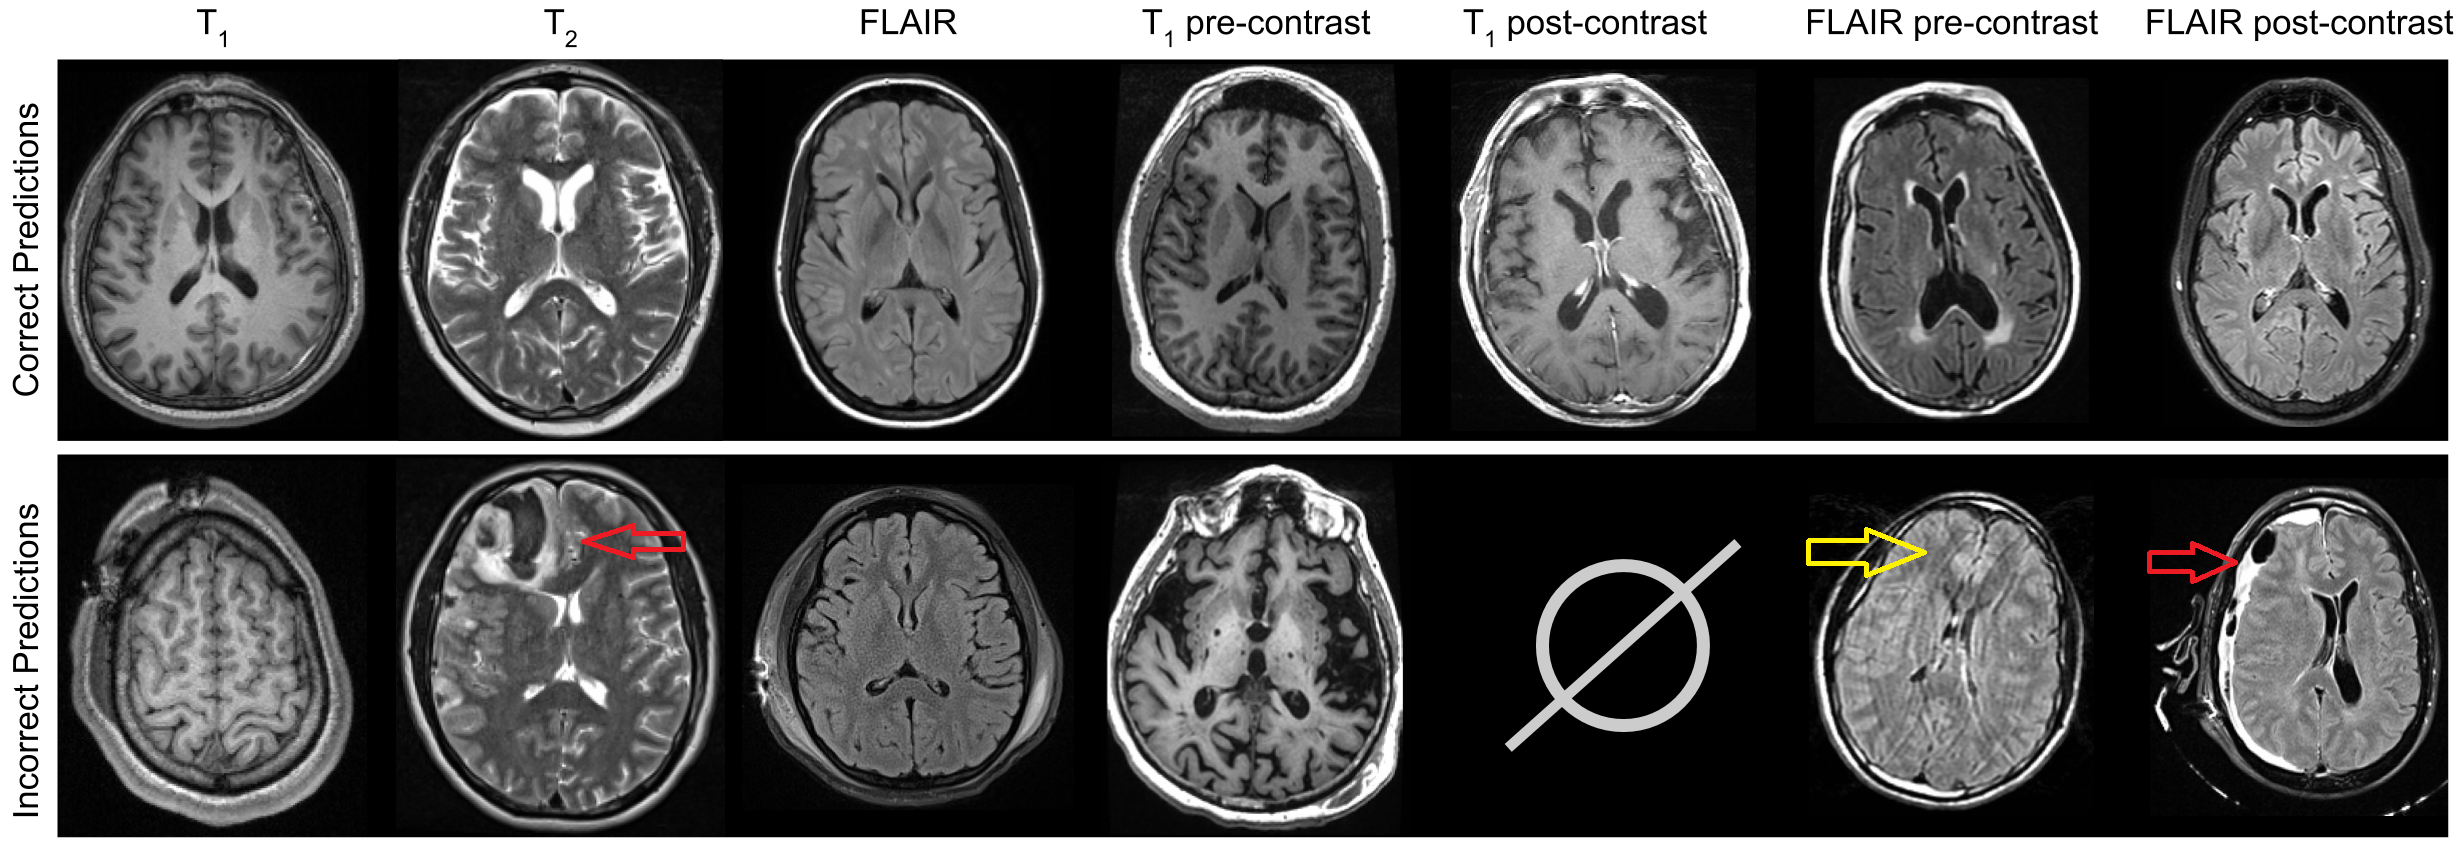

Refer to caption

Figure 3: Examples of correct and incorrect predictions by ΦΦ\Phi-Net are shown. First row indicates correct predictions, and the second row shows some errors. From left to right, the erroneous predictions made were: T2subscript𝑇2T_{2}, T1subscript𝑇1T_{1}, T1subscript𝑇1T_{1}, post-T1subscript𝑇1T_{1}, (no true post-T1subscript𝑇1T_{1} images were misclassified), post-FLAIR, and post-FLAIR. Note how the majority of misclassified images have artifacts (yellow arrow) or severe pathologies (red arrow).

Table 2 shows classification accuracy of ΦΦ\Phi-Net comparing with ResNet–. ΦΦ\Phi-Net outperforms ResNet– in all three classification tasks. ΦΦ\Phi-Net has a mean accuracy of 97.5797.5797.57% over all three tasks, while ResNet– has 95.4795.4795.47%. Although accuracies are high for both models, ΦΦ\Phi-Net produces more than a 333% improvement for the pre-FLAIR vs post-FLAIR classification, which is usually the most challenging task, even for a visual comparison. To compare the test performances between ResNet– and ΦΦ\Phi-Net, we performed McNemar’s test [16] over each of the three tasks, obtaining the p-values of 0.450.450.45, 0.0020.0020.002, and 0.0520.0520.052 for T1subscript𝑇1T_{1} vs T2subscript𝑇2T_{2} vs FLAIR, T1subscript𝑇1T_{1} pre vs post, and FLAIR pre vs post classifications, respectively. Therefore, ΦΦ\Phi-Net produces a significantly more accurate classification between pre and post-contrast images than ResNet–, while being similar in the case of the T1subscript𝑇1T_{1}-T2subscript𝑇2T_{2}-FLAIR classification task. Note that while the first task is comparatively easier, pre- vs post-contrast FLAIR identification can sometimes be difficult for a human observer, and ΦΦ\Phi-Net misclassified only 181818 of 294294294 images in this category.

Fig. 3 shows some classification examples from the test set, with the first row corresponding to correct classifications made by ΦΦ\Phi-Net and the second row showing the incorrect ones. Of the handful of classification errors that occurred, the majority suffered from imaging artifacts (Fig. 3 yellow arrow) or pathologies (Fig. 3 red arrow), which confounded the model’s ability to make accurate predictions. No post-contrast T1subscript𝑇1T_{1} images were misclassified. Although both of the CNN-based methods achieved more than 909090% accuracy, the registration and correlation based method achieved only an average of 81.1981.1981.19% accuracy on the T1subscript𝑇1T_{1}-T2subscript𝑇2T_{2}-FLAIR classification task. It classified 989898% of T2 images correctly and 727272% of both T1 and FLAIR images correctly. However, its 151515% average lower accuracy compared to the deep learning approaches indicates that the template-based classification is not as robust.